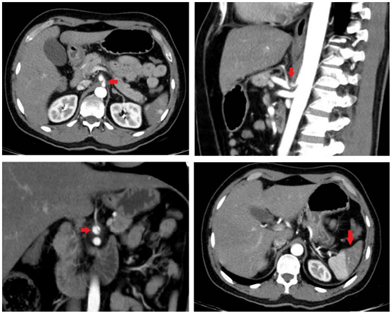

Por la persistencia del dolor se solicitó una tomografía computarizada contrastada de abdomen para descartar patología inflamatoria, encontrando múltiples infartos esplénicos y trastorno de la perfusión hepática, con aparente origen en un defecto de llenado lineal del tronco celíaco (figura 1). De manera consensuada con radiología se solicitó una angiotomografía para esclarecer la lesión vascular, encontrando una disección contenida del tronco celíaco y autolimitada a la arteria hepática común, después del origen de la arteria gástrica izquierda y antes del origen de la arteria gastroduodenal, sin presencia de aneurismas. No se encontró compromiso isquémico de las vísceras (figura 2).

Debido a la persistencia del dolor abdominal con episodios de gran intensidad, asociados a emesis, con alta sospecha de isquemia visceral en curso, se decidió realizar tratamiento endovascular, encontrando disección del tronco celíaco en su ostium y tercio proximal, el cual causaba una oclusión parcial y bajo flujo en la arteria hepática, con ausencia de flujo en la arteria gastroduodenal. Se practicó una angioplastia con balón e implantación de una prótesis de 7 x 27 mm, mejorando el flujo de los vasos distales, sin estenosis residual y sin complicaciones asociadas.